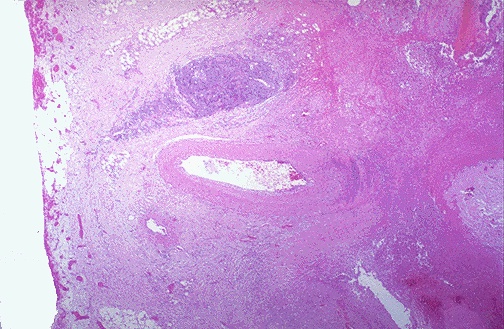

Disease Processes & Lesion Recognition

Examine each slide systematically — architecture first, then cellular detail — before reading the annotated lesson notes.